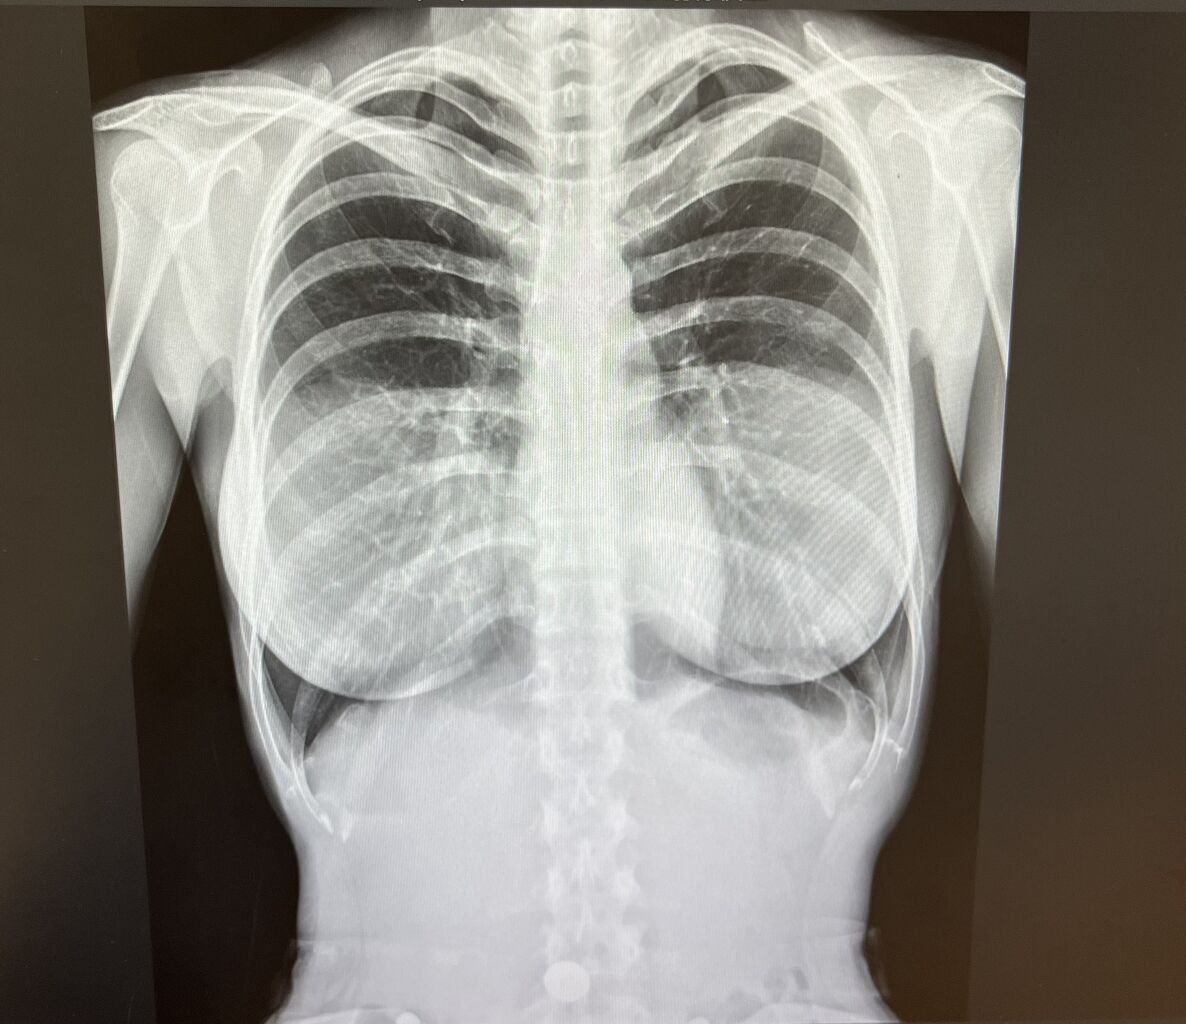

グラビアアイドルさん、レントゲン写真をアップするも“アレ”が透けて見えてしまう

シリコンバッグ映ってて草

入れ乳だとこのように映るらしい

豊胸じゃないアピールやぞ

こんな写真見ただけで肺に炎症があるかどうか判読できる医者ってすげぇと思うわ

俺にはそもそもどこら辺に肺が写ってるのかすら見えんしもみあげる名無し at 2026年01月25日 03:40 ID:.Wq6bap70 -

>>4

肺炎だと白くなるからねat 2026年01月25日 03:56 ID:OyY1EJeb0 -

X線写真は2次元のようで「厚み」の情報もあるから

AI技術で肌色の3Dデータを作ることができるだろうね

あと医者の目で見てある「軽微な病変」が気になるけど言えないね

みなさんも医療データのアップはしないようにねもみあげる名無し at 2026年01月25日 09:38 ID:lZgAeTxe0 -